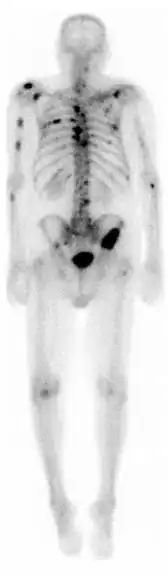

![]() A nuclear medicine whole-body bone scan. The nuclear medicine whole-body bone scan is generally used in evaluations of various bone-related pathology, such as for bone pain, stress fracture, nonmalignant bone lesions, bone infections, or the spread of cancer to the bone. | |

A bone scan or bone scintigraphy /sɪnˈtɪɡrəfi/ is a nuclear medicine imaging technique used to help diagnose and assess different bone diseases. These include cancer of the bone or metastasis, location of bone inflammation and fractures (that may not be visible in traditional X-ray images), and bone infection (osteomyelitis).[1]

Nuclear medicine provides functional imaging and allows visualisation of bone metabolism or bone remodeling, which most other imaging techniques (such as X-ray computed tomography, CT) cannot.[2][3] Bone scintigraphy competes with positron emission tomography (PET) for imaging of abnormal metabolism in bones, but is considerably less expensive.[4] Bone scintigraphy has higher sensitivity but lower specificity than CT or MRI for diagnosis of scaphoid fractures following negative plain radiography.[5]